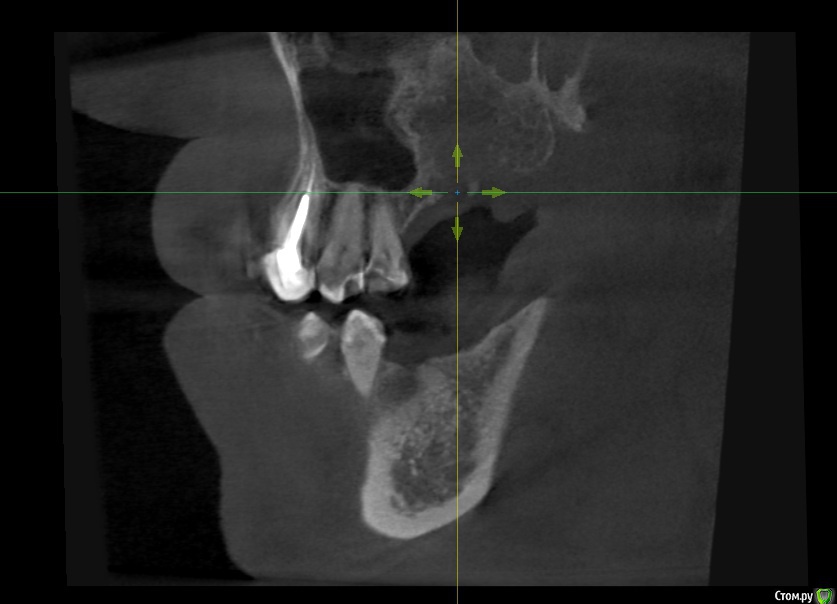

alboard Опубликовано 9 марта, 2017 Поделиться Опубликовано 9 марта, 2017 В области 16,17,18 дно отсутствует. Какая здесь может быть тактика? Ссылка на комментарий

Dok22 Опубликовано 9 марта, 2017 Поделиться Опубликовано 9 марта, 2017 В пазухе какое то образование. 1 Ссылка на комментарий

mr.Fog Опубликовано 9 марта, 2017 Поделиться Опубликовано 9 марта, 2017 Скорее всего это кальцифицированные останки радикулярной кисты. Ссылка на комментарий

Oscar Опубликовано 9 марта, 2017 Поделиться Опубликовано 9 марта, 2017 давно зубы удалены? Похоже на ретенционную кисту пазухи... Можно попробовать отслоить шнайдер снизу, если перфорация выход только "парашют"... Ссылка на комментарий

drpetrovich Опубликовано 13 марта, 2017 Поделиться Опубликовано 13 марта, 2017 Действительно по томограмме больше похоже на резидуальную кисту, т.е. при зондировании проваливаешься не в пазуху, а в полость кисты. Отделяемое было кстати? Вопрос про давность удаления актуален. Ссылка на комментарий